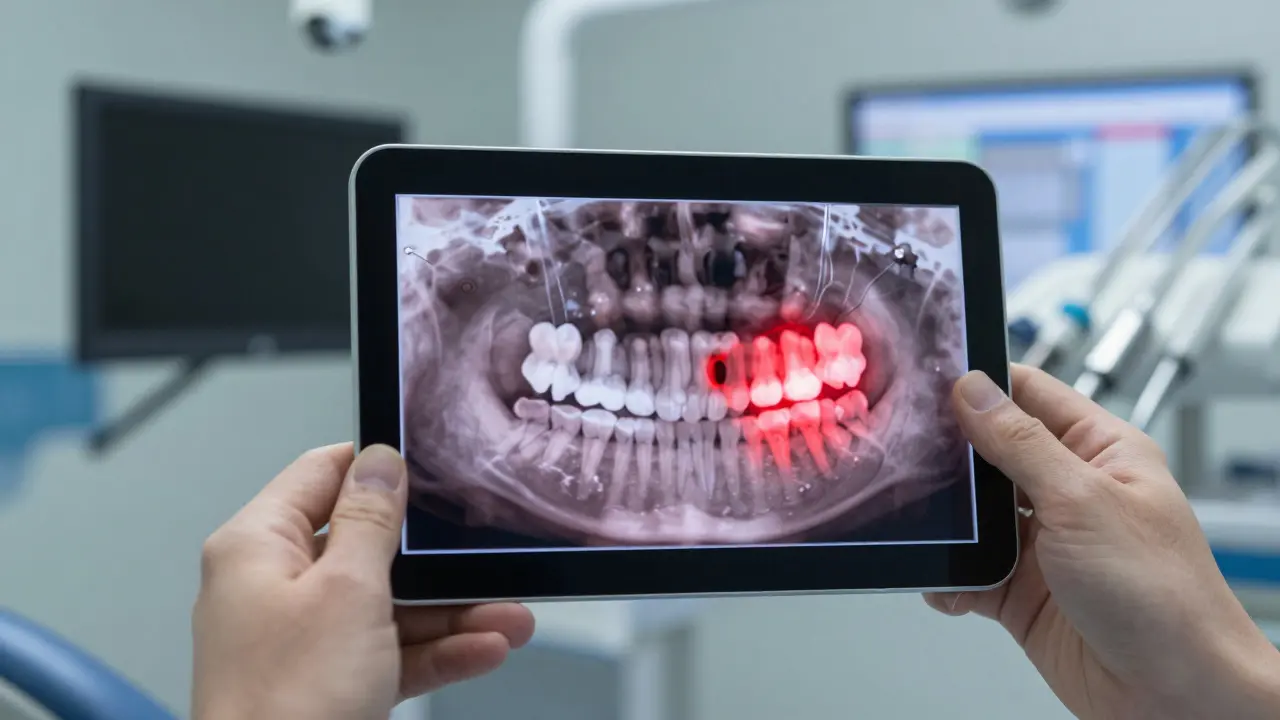

Skrytý mezizubní kaz mezi zubem moudrosti a sousedním zubem, znázorněný temnými stíny šířícími se po sklovině.

1. Přijďte na vyšetření k zubnímu lékaři. Rentgen je klíčový. Jen na základě pohledu do úst se nedá říct, zda je zub zatlačený, jak je orientovaný, a zda hrozí poškození sousedního zubu.

2. Požádejte o 3D snímek (panoramatický snímek nebo CT). Pokud máte podezření na komplikace, moderní zubní kliniky používají 3D snímky, které ukazují přesnou pozici zubu vůči nervům a kosti.

3D rentgenový snímek impaktovaného zubu moudrosti tlačícího na sousední zub, s označenými oblastmi poškození.